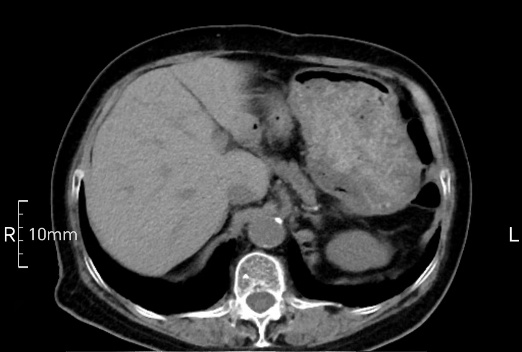

看看下面三幅便知遵醫囑的重要性。

沒禁食,胃內全是食物,導致胃壁顯示不清。